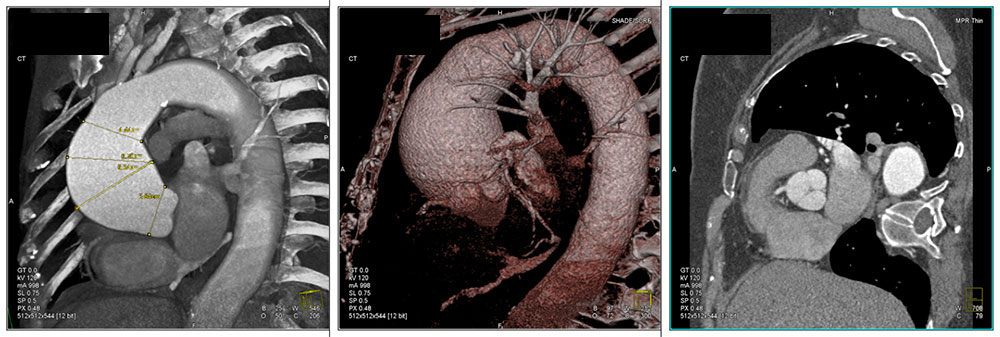

Dilated Aortic Root

68 year old female with no history of surgical repair. 3D maps and reformatted images show dilatation of the supravalvular aortic root and ascending aorta characteristic of annuloaortic ectasia. Operative repair is indicated when aorta reaches a diameter of 5 cm due to high risk of rupture. Classic “tulip bulb” configuration.